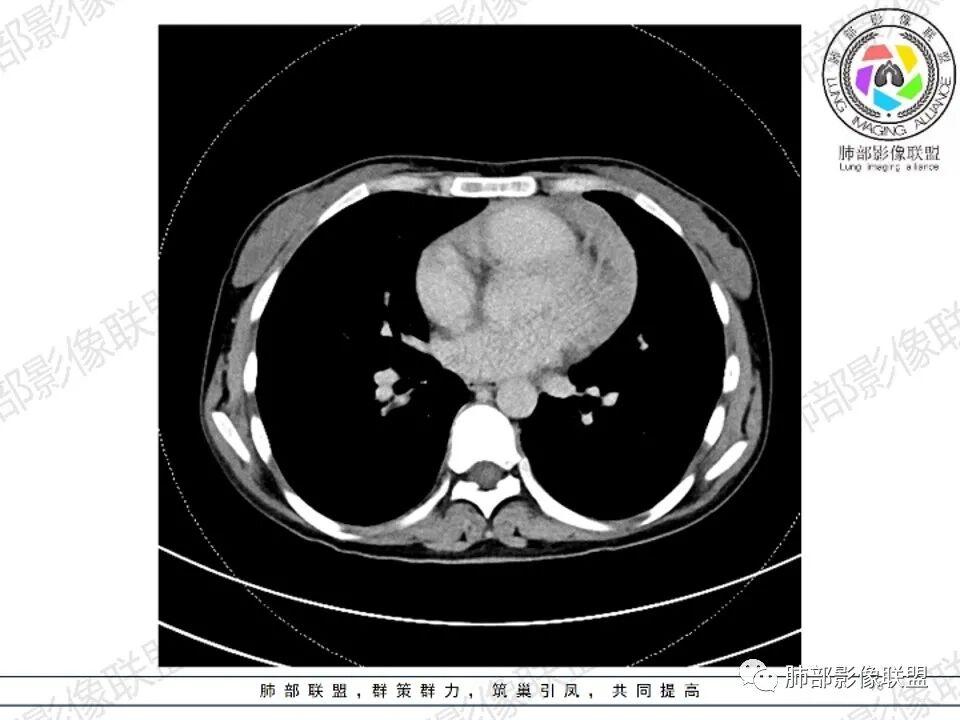

纵隔多发结节堆积 塑型生长  质软 边界不清 强化不均  双侧腋窝淋巴结肿大

年轻女性,贫血伴乏力,前纵隔占位,多发结节融合成块,爬孵感,边界模糊,不均匀强化,中心坏死,内可见血管造影,部分侵犯心包,双侧腋窝多发肿大淋巴结,首先考虑淋巴瘤

年轻女性,贫血,CT示前纵隔团片状软组织占位,多结节堆积感,塑形生长,边界欠清,包绕大血管及心包,增强明显不均匀强化,内见血管漂浮。纵隔4R,5,7区及双侧腋窝多发肿大淋巴结,综合考虑为淋巴瘤可能

前纵隔不规则肿块,多结节融合,边界欠清,延周围脂肪间隙生长,包绕主动脉及肺动脉血管,平扫密度欠均匀,增强扫描可见多发低密度坏死,并可见一条血管穿行,腋窝多发大小不等淋巴结肿大,年轻女性,考虑恶性:淋巴瘤,胸腺癌,肉瘤,浆细胞瘤

女,27,间断头晕、乏力3年,左眼视物模糊2月。贫血。胸部CT:前纵隔不规则肿块,多结节融合,边界不清,沿主动脉及肺动脉间隙生长,平扫密度欠均匀,增强扫描可见多发低密度坏死,纵隔血管供血穿行,腋窝多发大小不等淋巴结肿大。考虑恶性病变,胸腺癌?肉瘤?淋巴瘤?鉴别胸腺瘤、结节病等。

前纵隔和双侧腋窝多发的淋巴结肿大,前纵隔为甚,融合呈中等强化,部分坏死呈低密度,包埋肺动脉主干和左心缘,融合斑块状,内见血管飘浮特点,前纵隔脂肪间隙混浊,首选淋巴瘤!

CT:定位纵膈病变,前中纵隔多发肿块,质软,塑形,密度不均匀,边界清楚。增强不均匀强化,坏死边界清楚,血管漂浮征。双侧腋下多组淋巴结肿大,明显异常强化。

2.影像显示前纵隔不规则块状影,依势贴附心脏大血管旁,密度不均,边界不甚清楚,有结节融合感。

3.病灶轻度不均匀强化,可见血管穿行,散在液性低密度区。

双肺门未见肿大淋巴结。

4.双侧腋窝区见增大淋巴结,边界清楚。

1.年轻女性,前纵隔不规则块状影,密度不均,边界不甚清楚,有结节融合感,轻度不均匀强化,可见血管穿行,最常见最符合的无疑是淋巴瘤!